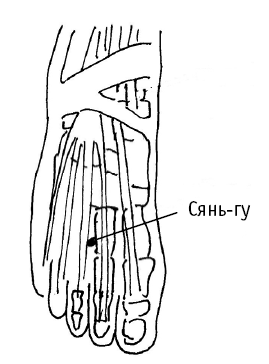

Юн-цюань («бурлящий источник, родник») расположена в середине подошвы, между 2-й и 3-й плюсневыми костями, в углублении, образующемся при поджатии пальцев стопы (в углублении в середине подошвы).

Дополнительный эффект от воздействия на юн-цюань: точку используют в критических состояниях (отравление, судороги); при ломоте в пояснице и коленях, головной боли, головокружении, шуме в ушах, бессоннице, сердцебиение, снижении памяти, нарушении мочеиспускания; при кашле, сухости во рту и в горле, нервных болезнях и многих других.

Юн-цюань («бурлящий источник, родник») расположена в середине подошвы, между 2-й и 3-й плюсневыми костями, в углублении, образующемся при поджатии пальцев стопы (в углублении в середине подошвы).

Дополнительный эффект от воздействия на юн-цюань: точку используют в критических состояниях (отравление, судороги); при ломоте в пояснице и коленях, головной боли, головокружении, шуме в ушах, бессоннице, сердцебиение, снижении памяти, нарушении мочеиспускания; при кашле, сухости во рту и в горле, нервных болезнях и многих других.